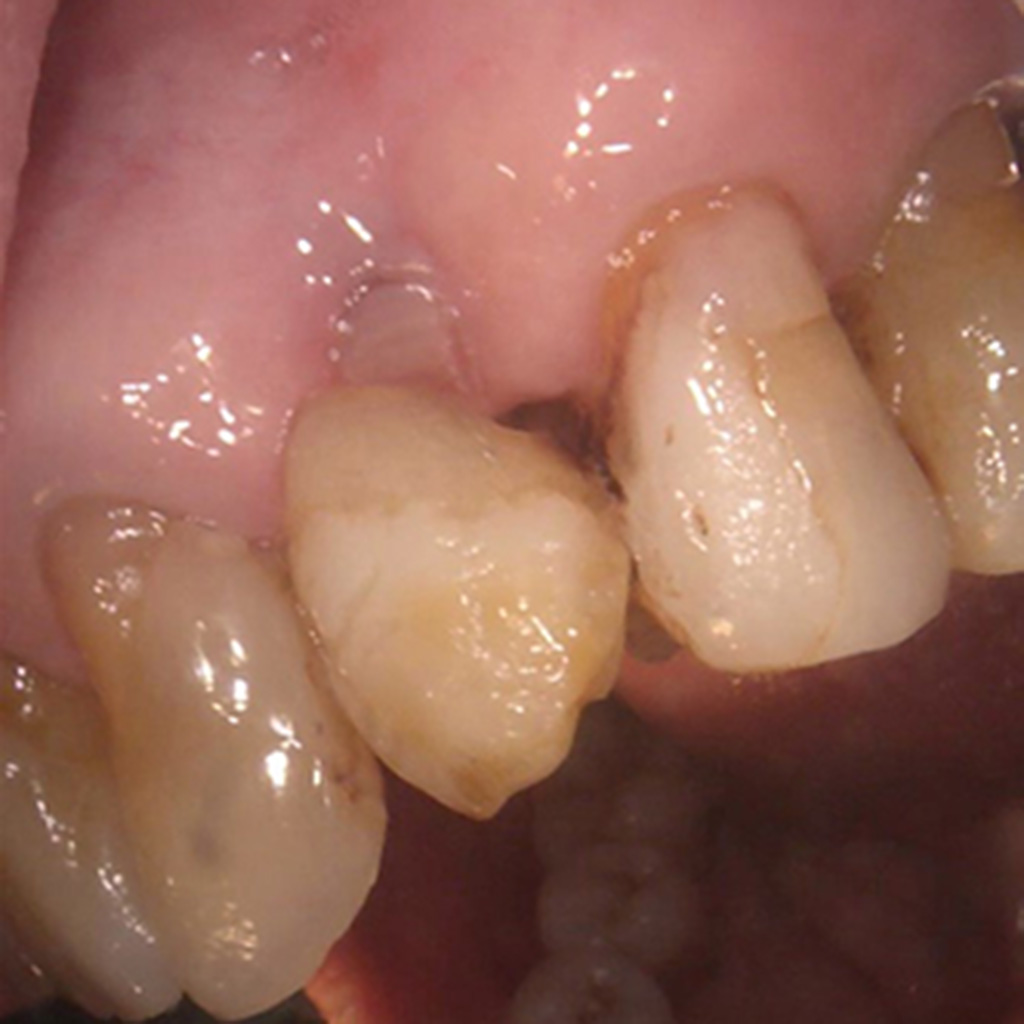

ある70歳代の女性患者さん(左上3インプラント、約10年前に他院で埋入)が

初診で来院され、患者さんから

「インプラントをしてもらった医院は閉院していて、何かあっては困るからインプラント部位は何も触らないで欲しい」

と強く要望されていました。

そのため初診から1年2ヶ月のインプラント部の関わりは

患者さん自身、インプラント部に自覚症状はありません。

患者さんの「触らないで」の要望でこれまで避けていたプロービングを、知識に基づき説明し実施しました。

口蓋側近心部でのみ6mmのポケットを確認しました。

出血や排膿、浸出液は確認されませんでした。